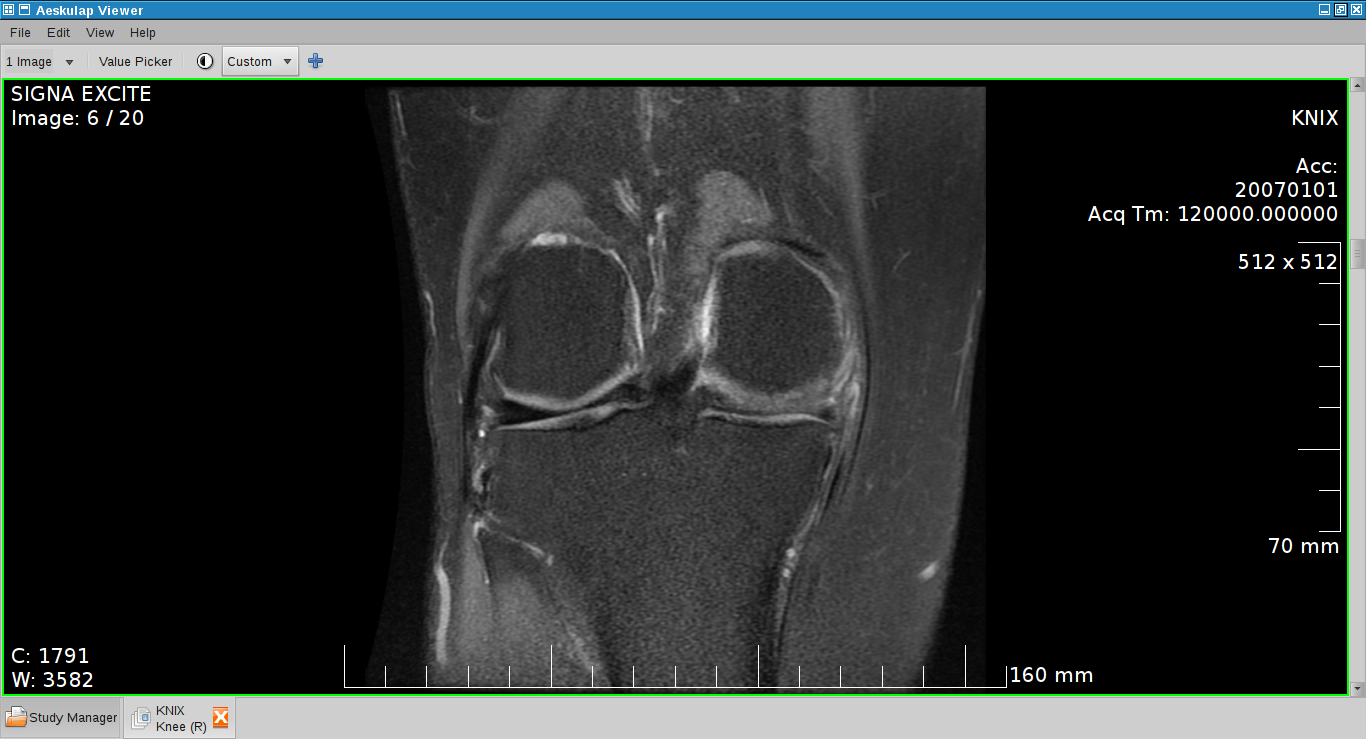

Ένας από τους λόγους που ακόμη χρησιμοποιώ Virtual Machine στο ιατρείο είναι για να βλέπω εικόνες από ιατρικές εξετάσεις και κυρίως από αξονική τομογραφία. Οι εικόνες είναι μορφή Dicom. Στα Windows το CD "παίζει" κατευθείαν με ένα ενσωματωμένο Viewer. Στο Ubuntu είχα σοβαρό πρόβλημα γιατί τα διάφορα προγράμματα (Aeskulap, Mayam etc) δούλευαν ανάλογα με την πρόγραμμα του αξονικού.

Τελευταία βρήκα ένα φοβερό cross-platform πρόγραμμα που δουλεύει πάντα. Είναι το Mevislab, δωρεάν, κλειστού κώδικα, modular. Είναι και επεξεργαστής εικόνας, όχι μόνο Viewer εξ΄ου και το τεράστιο μέγεθος ~2gb. Είναι λίγο θέμα να καταλάβεις στην αρχή πως δουλεύει αλλά όπως λένε "If everything fails read the manual"!

Μετά από ψάξιμο κατέληξα σε 2 δωρεάν, το ένα opensource, cross-platform, προγραμματάκια που τρέχουν άψογα στο Ubuntu.

Το ένα είναι το Mango. Δωρεάν, java based, κλειστού κώδικα απίστευτα ελαφρύ και γρήγορο.

Μειονεκτήματα: Δεν διαβάζει subfolders & compressed Dicom εικόνες.

Το άλλο είναι το Gimias, ανοικτού κώδικα και διαβάζει τα πάντα.

Μειονέκτημα: Κολλά καμιά φορά γιατί τρώει όλη τη ram.